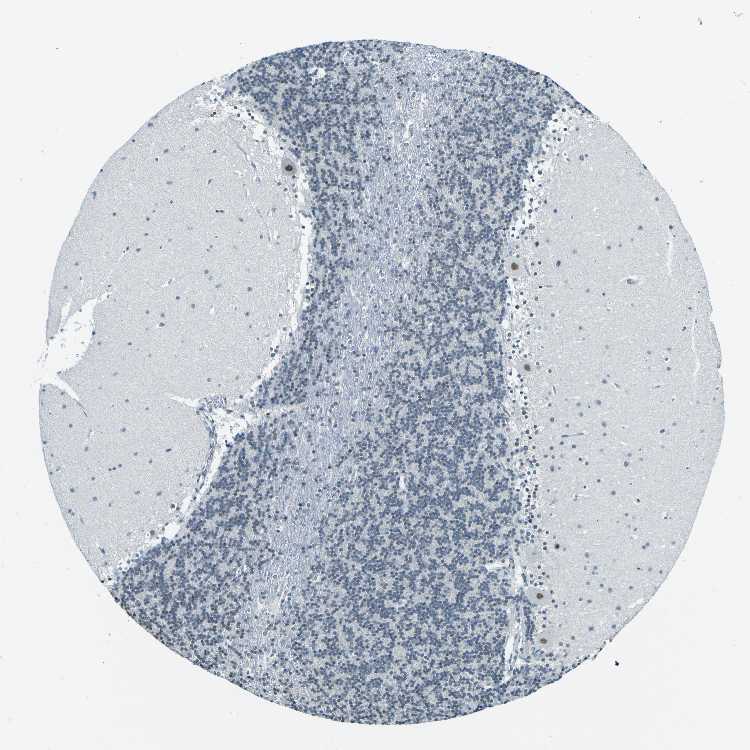

CEREBELLUM - Antibody stainingi

Antibody staining in the annotated cell types in the current human tissue is reported as not detected, low, medium, or high, based on conventional immunohistochemistry profiling in selected tissues. This score is based on the combination of the staining intensity and fraction of stained cells.

Each image is clickable and will lead to virtual microscopy that enables deeper exploration of all samples and also displays staining intensity scores, fraction scores and subcellular localization as well as patient and tissue information for each sample.

Antibody HPA012024

Purkinje cells Medium

Cells in granular layer Not detected

Cells in molecular layer Not detected